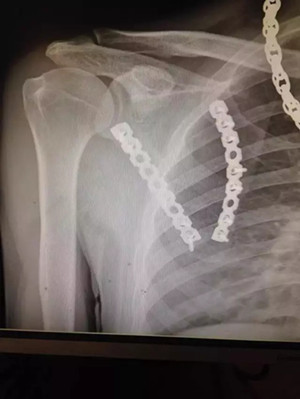

患者小陳(化名)因車禍致肩部受傷到廣安醫(yī)院就診,被診斷為“左側(cè)肩胛骨粉碎性骨折”,骨折端分離移位明顯。

術(shù)后拍片